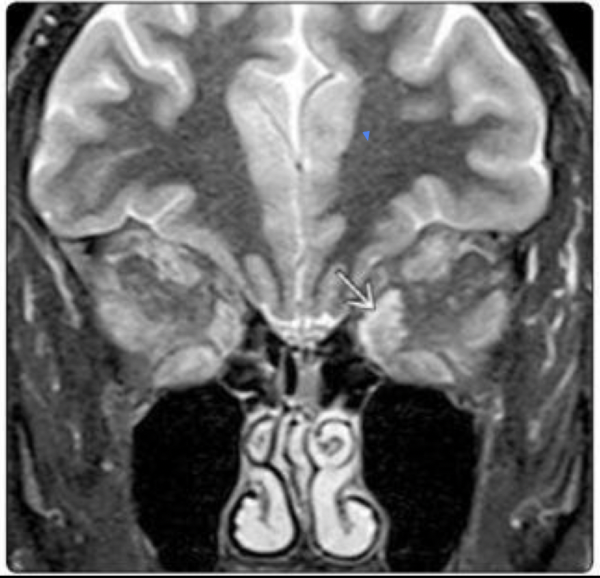

8

¿qué enfermedad sospechas?

A

Orbitopatía tiroidea